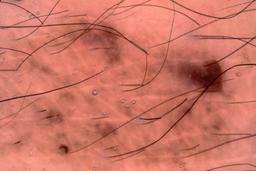

{

"age_approx": 85,

"anatom_site_general": "head/neck",

"concomitant_biopsy": false,

"dermoscopic_type": "contact non-polarized",

"diagnosis_1": "Benign",

"diagnosis_2": "Benign melanocytic proliferations",

"diagnosis_3": "Nevus",

"diagnosis_confirm_type": "single image expert consensus",

"image_type": "dermoscopic",

"lesion_id": "IL_9360350",

"patient_id": "IP_6191697",

"sex": "male"

}